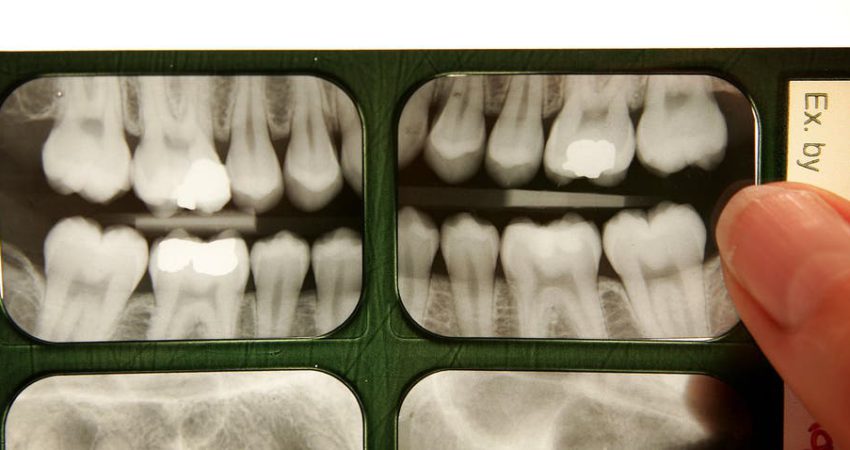

Në studimin aktual, të botuar në revistën “Science Advances”, shkencëtarët analizuan kafkat e shimpanzeve meqë konsiderohen si primitivët e njerëzve dhe zhvilluan një model që shpjegon koordinimin midis rritjes së fytyrës dhe mekanizmit të muskujve të përtypjes. Për shkak të një veprimi delikat midis ritmit të rritjes së muskujve të fytyrës dhe daljes së dhëmbëve të pjekurisë ata thonë se këta dhëmbë dalin vetëm kur krijohet një hapësirë e mjaftueshme “mekanikisht e sigurt” për të dalë.!

Nëse dhëmbët e pjekurisë dalin “para afatit”, thonë studiuesit, dhëmbët do të prishin funksionin e të gjithë aparatit të përtypjes dhe do të shkaktojnë dëme në nofull.

Meqenëse dhëmbët e pjekurisë nuk dalin deri në një pikë kur ka ndodhur një rritje e mjaftueshme e fytyrës, shkencëtarët besojnë se “detajet më të imta të modelit mund të eksplorohen në më shumë mostra për të ndihmuar në kuptimin e fenomenit të ndikimit të dhëmbëve tek njerëzit”.

Ekspertët thonë se tek njerëzit, dalja e vonuar e dhëmbëve është rezultat i evolucionit të rritjes së përgjithshme të ngadaltë të fytyrës të shoqëruar me nofulla të shkurtra.

“Rezulton se nofullat tona rriten shumë ngadalë, ka të ngjarë për shkak të historive tona të përgjithshme të ngadalta të jetës dhe në kombinim me fytyrat tona të shkurtra, vonohen kur një hapësirë mekanikisht e sigurt është në dispozicion”, thotë Gary Schwartz, një tjetër bashkë autor i studimit.